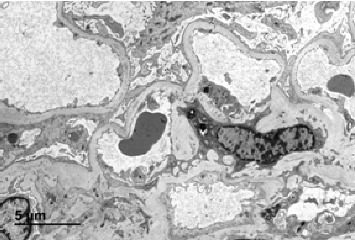

Collagen IV pathogenic variants are present in Alport syndrome (AS) and some forms of familial focal segmental glomerulosclerosis (FSGS). These conditions pose diagnostic challenges due to overlapping clinical, histological, and genetic features. Ocular coherence tomography (OCT) has emerged as a pivotal diagnostic tool by revealing ocular manifestations characteristic of AS. Here, we present two cases initially diagnosed with primary FSGS but later found to harbor collagen IV pathogenic variants. Both cases progressed to end-stage kidney disease (ESKD) needing transplantation. OCT revealed severe temporal macular thinning consistent with AS in both cases. Our findings highlight the critical role of OCT in distinguishing the subtle differences in the presentation of collagen IV nephropathies. OCT proves valuable for clinicians, particularly when COL4 nephropathies present ambiguous or overlapping features. In such instances, OCT serves to establish precise diagnoses, preventing unnecessary immune suppression. Therefore, incorporating OCT alongside genetic and histological evaluations is crucial for accurate diagnosis, management, and appropriate genetic counseling. Furthermore, recognizing the prevalence of AS accurately is pivotal for conducting population-based studies, which are essential for advancing our understanding of the condition, improving patient care, and informing future research initiatives.